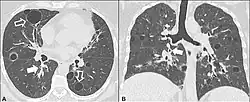

Lung cysts

A lung cyst, or pulmonary cyst, encloses a small volume of air, and has a wall thickness of up to 4 mm.[3] A minimum wall thickness of 1 mm has been suggested,[3] but thin-walled pockets may be included in the definition as well.[4] Pulmonary cysts are not associated with either smoking or emphysema.[5]

A lung cavity has a wall thickness of more than 4 mm.[3]